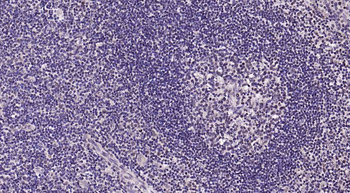

100 μl, 200 μl, 50 μl - RORC Rabbit Polyclonal Antibody [orb6888]Featured

FC, ICC, IF, IHC-Fr, IHC-P, WB

Human, Mouse, Rat

Bovine, Canine, Equine, Gallus, Porcine, Rabbit

Rabbit

Polyclonal

Unconjugated

50 μl, 100 μl, 200 μl - Featured